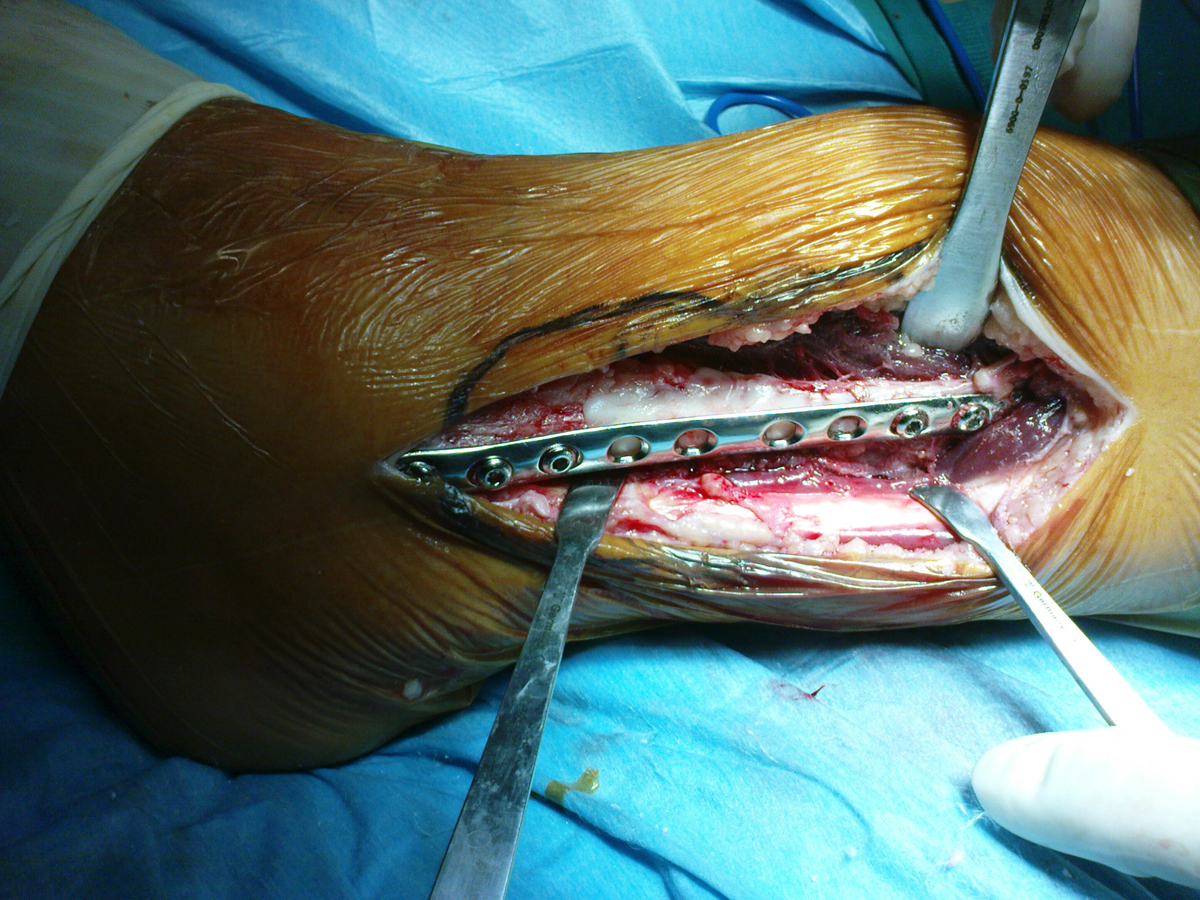

• Οστεολυτική εξεργασία περόνης